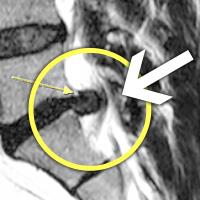

MRI ġ